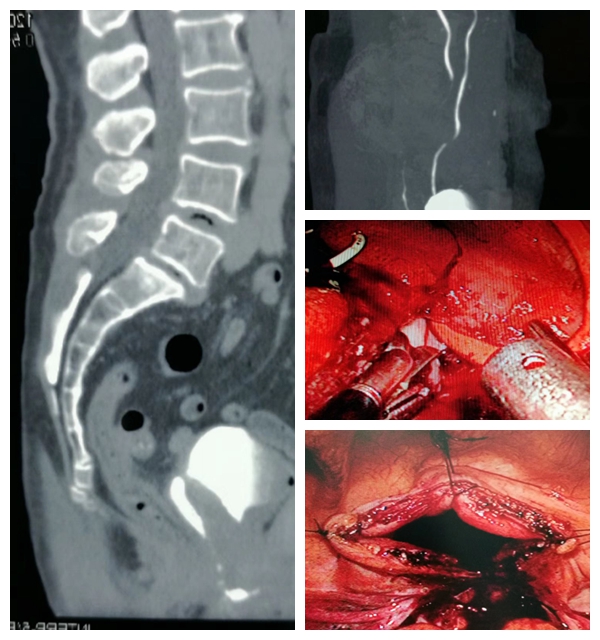

腹腔镜下离断式肾盂输尿管成型术治疗小儿肾盂输尿管交接部狭窄的病例

科室积致力于泌尿外科微创技术的创新和优化。在广泛开展腹腔镜肾癌根治术、肾部分切除术、前列腺癌根治术、全膀胱切除术及肾上腺肿瘤切除术等基础上,进一步扩大腹腔镜技术的覆盖范围,开展腹腔镜下腹膜后和盆腔扩大淋巴结清扫术等高难度手术。推动外科微创化与加速康复外科(ERAS)的紧密结合,打造成特色、优势技术,受到广大患者认可。泌尿系统结石疾病的诊治是我科的传统优势项目,保持着省内先进水平。我科应用经皮肾镜技术开展了一些高难度的肾结石手术,如严重脊柱畸形患者的肾结石、孤立肾肾结石、无肾积水的肾结石、马蹄肾肾结石等,而且手术均取得成功。泌尿系肿瘤的发病率逐年升高,其防治任重而道远。我科积极开展复杂性泌尿系肿瘤的诊治,尤其是巨大肾上腺肿瘤、巨大肾肿瘤、孤立肾较大肾癌的保留肾脏手术等。同时积极开展泌尿系肿瘤的防治研究,重点进行泌尿系肿瘤病因学的研究,尤其是寻找膀胱癌、肾癌和前列腺癌相关功能基因,从基因学角度寻找肿瘤特异标记物,提高泌尿系肿瘤早期诊断水平,并为进一步基因治疗提供基础。前列腺增生作为老年男性常见疾病一直以来是我们重点研究的方向和医疗特色之一。随着外科技术的不断进步及新的医疗设备的不断涌现和完善,TURP的金标准地位逐渐受到挑战,如经尿道钬激光前列腺剜除术技术日臻完善,大有取代TURP之势。目前我科已积极开展经尿道钬激光在良性前列腺增生治疗中的应用,取得了良好的治疗效果。我科针对目前男性疾病诊治需求量迅速增加的现状,积极开展男科的特色诊疗,范围包括男子勃起功能障碍、早泄、男性不育症、精索静脉曲张、血精、阴茎硬结症、睾丸附睾疾病、男子生殖系统内分泌疾病等。开科以来典型手术介绍如下: